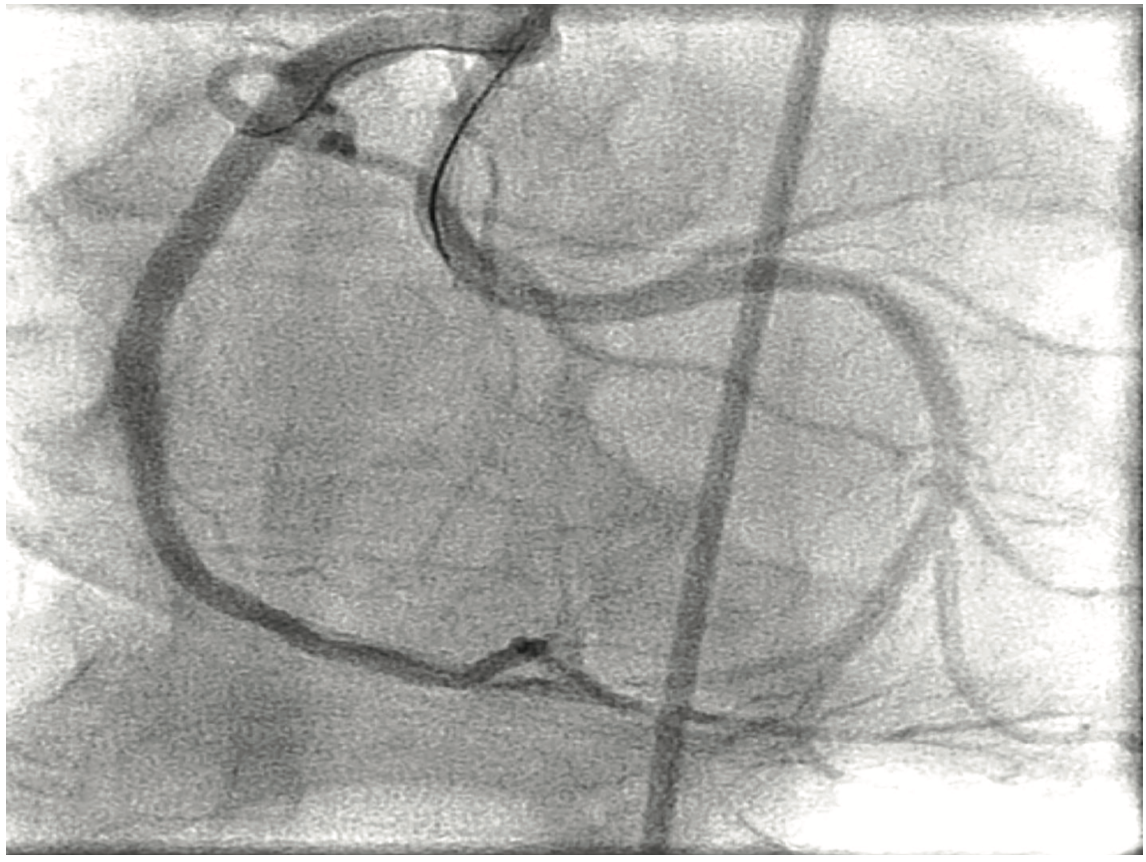

Figure 2. Left anterior oblique (LAO) projection: Patent right coronary artery (RCA) and LCX seen originating from main RCA.

A 56-year-old male presented with unstable angina pectoris. He had known severe anomalous LCX disease managed medically thus far. Past medical history was also significant for hypertension, hyperlipidemia, and diabetes. Cardiovascular physical examination was unremarkable. An electrocardiogram (EKG) showed sinus bradycardia and diffuse, mild ST segment elevations. An echocardiogram showed normal left ventricular systolic function and no pericardial effusion. Troponin I level was initially normal. The patient was treated with heparin, nitroglycerin, beta-blocker, statin, and aspirin. Coronary angiography showed non-obstructive disease in the left anterior descending artery (LAD); the LCX was not visualized on the left system injection (Figure 1 shows the right anterior oblique [RAO] caudal projection). The RCA was dominant with normal take-off and no obstructive disease noted; however, the LCX was seen coming off the proximal part of RCA, and was noted to be severely and diffusely diseased. The mid LCX had a 95-99% stenosis and distal segments with less severe but also obstructive disease in the proximal portion (Figure 2 is the left anterior oblique [LAO] straight projection). The LCX had a culprit lesion that we decided to stent. A 6 French multipurpose guide catheter (Multipurpose [MP] 2 [Boston Scientific]) was inserted via right femoral artery access. This catheter has a tendency for deep intubation of the RCA (Figure 3). In order to avoid an unfavorable prolapse into the take-off of the LCX on pullback (there is a right angle between the proximal LCX and the guide, thus increasing the risk of LCX guide dissection), a Balance Middleweight (BMW) guide wire (Abbott Vascular) was placed into the distal RCA branch. Its distal end was looped (into a “knuckle”). The wire was pushed forward and in doing so, the guide catheter was pushed in a controllable manner out of the RCA to the level of the LCX take-off. Once at this level, the LCX was wired with another BMW guide wire (Figure 4). The LCX was predilated with a 2.0 x 15 mm balloon and then stented with a Xience Prime 2.75 x 38 mm stent (Abbott Vascular) (distal and mid portions) and 2.75 x 18 mm (proximal) stents at high pressure. The result was satisfactory (Figure 5, Video 1).